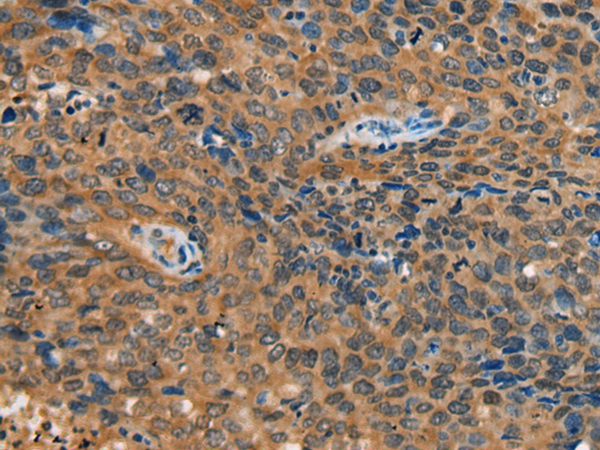

图片:

The image on the left is immunohistochemistry of paraffin-embedded Human cervical cancer tissue using 46714(YTHDF1 Antibody) at dilution 1/55, on the right is treated with synthetic peptide. (Original magnification: x200)